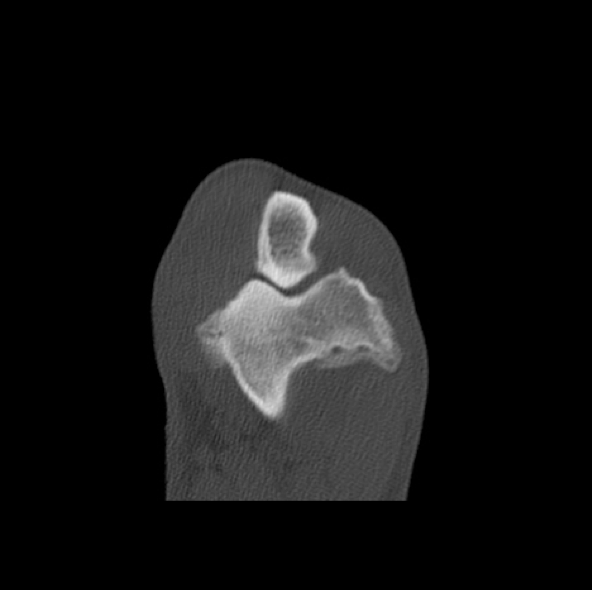

In den nächsten Tagen erhielt der Hund ein Schmerzmittel und Hyaluronsäure zum Knorpelaufbau und ging regelmäßig zur Physiotherapie. Aaron lief vier Wochen lahmfrei ohne Schmerzmittel. Danach ging er wieder zunehmend lahm. Er zeigte wieder deutliche Gelenkergüsse in beiden Ellenbögen. Es wurde eine Computertomographie-Untersuchung (CT) beider Ellenbögen durchgeführt. Im CT wurden mehrere osteophytäre Zubildungen (Arthrosen) am Gelenk diagnostiziert, welche infolge des permanenten Entzündungsreizes entstanden sind. Weitere knöcherne Veränderungen und eine erneute abgelöste Knorpelschuppe (OCD) konnte nicht gefunden werden.